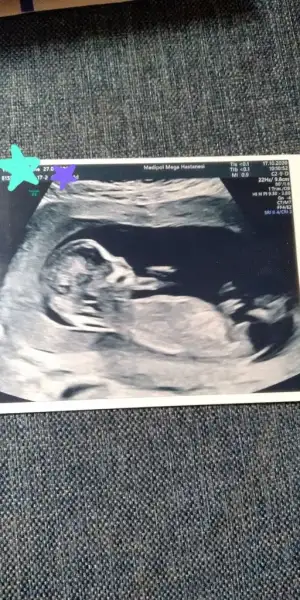

Gözün aydın canım erkekte değişme olmaz. Bana da %80 demiş bu haftalarda belli artık. İnsaallah vaktinde alırsın kucağınaKızlar çok şükür herşey yolunda ikili test dedi ama doktor detaylı ultrason gibi inceledi kalp böbrek mide eller ayaklar kemikler çok memnun kaldım %80 erkek dedi cinsiyetinede büyük ihtimal degimez bir dahaki kontrole dahada netleşir dedi. Benim kızımda serklaj olduğum için tekrar 23 ekime serklaj tarihi verildi rahim ağzına dikiş atılacak onda da antrenmanlıym inşallah bu bebegimide vaktinde sağlıklı kucağıma alırım.

Biz de bugün doktora gittik 16+2 kesin kız dedi zaten güveniyordum 12. Haftada söylediğine..Şükür herşey yolunda 148 Gr olmuş zillim ..Bir ay sonra ayrıntili çekilecek onun için perinatalog isimleri verdi..Hepsi özel istersen çapa Cerrahpaşa kanunide de yaptırabilirsin dedi ama onlarda ilk kadın doğuma muayene olup sevk açtırmak lazım uzun iş yani..Bir yeri aradım 600 TL dediler Şişli de yeri.. Bakalım hayırlısı. Resmimizi de gösterelim size![]()